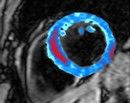

Pentru realizarea noului studiu, cercetatorii au folosit imaginile captate prin rezonanta magnetica (MRI) pentru a examina sangerarea din interiorul inimii, in cazul a 15 indivizi care au suferit recent un infarct.

Astfel, imaginile sugerau ca pacientii care au suferit un infarct de intensitate mare, in timpul caruia mai multi muschi ai inimii au fost afectati, sangerarea era mai abundenta decat in cazul celor care au suferit un infract relativ mai mic.